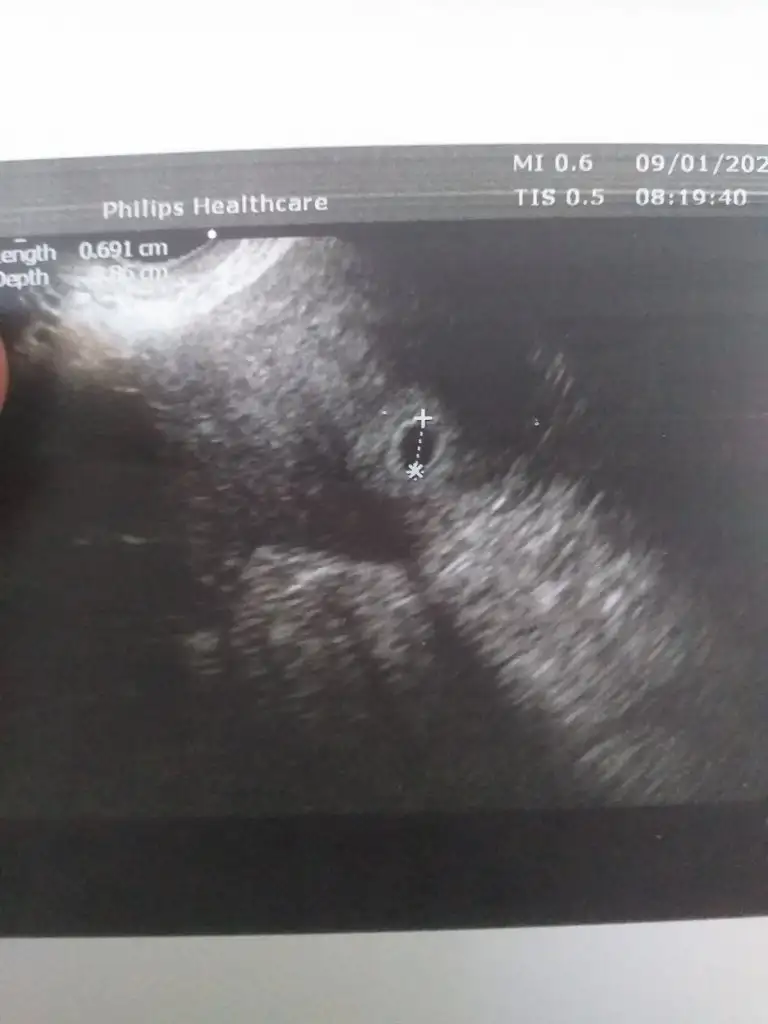

4+6 kesemin görüntüsü. Bir sonraki kontrolde bebeği ve kalp atımını görmüştük.(5+5)kızlar kese resımlerınızı atarmısınız benımkı cok mınık ılk gordugunuz resımlerı